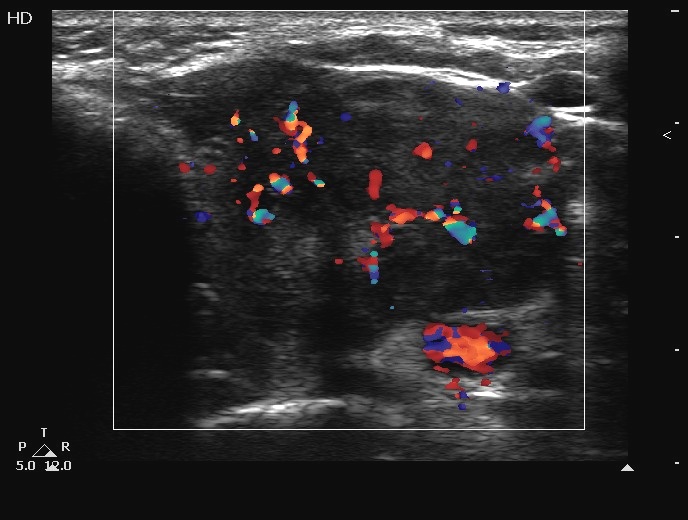

Ultrasonography. The thyroids were echonormal and contained several cystic areas and an echonormal nodule in the right lobe. There was a large partly echonormal, partly hypoechogenic nodule in the left thyroid. This lesion had irregular bordersr and presented an irregularly increased intranodular vascularization.